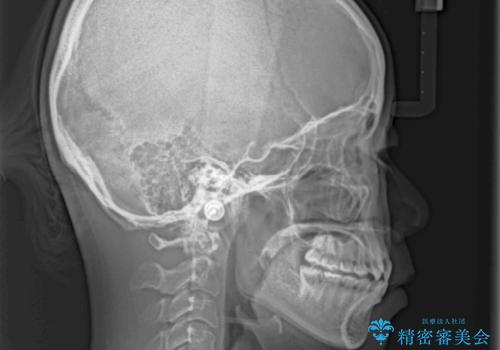

- 前歯のデコボコと上下のクロスバイトを気にして来院された患者様です。

インビザラインを用い、IPR(歯と歯の間を削る)と歯列全体を拡大させることで、歯並びを整えていくこととしました。